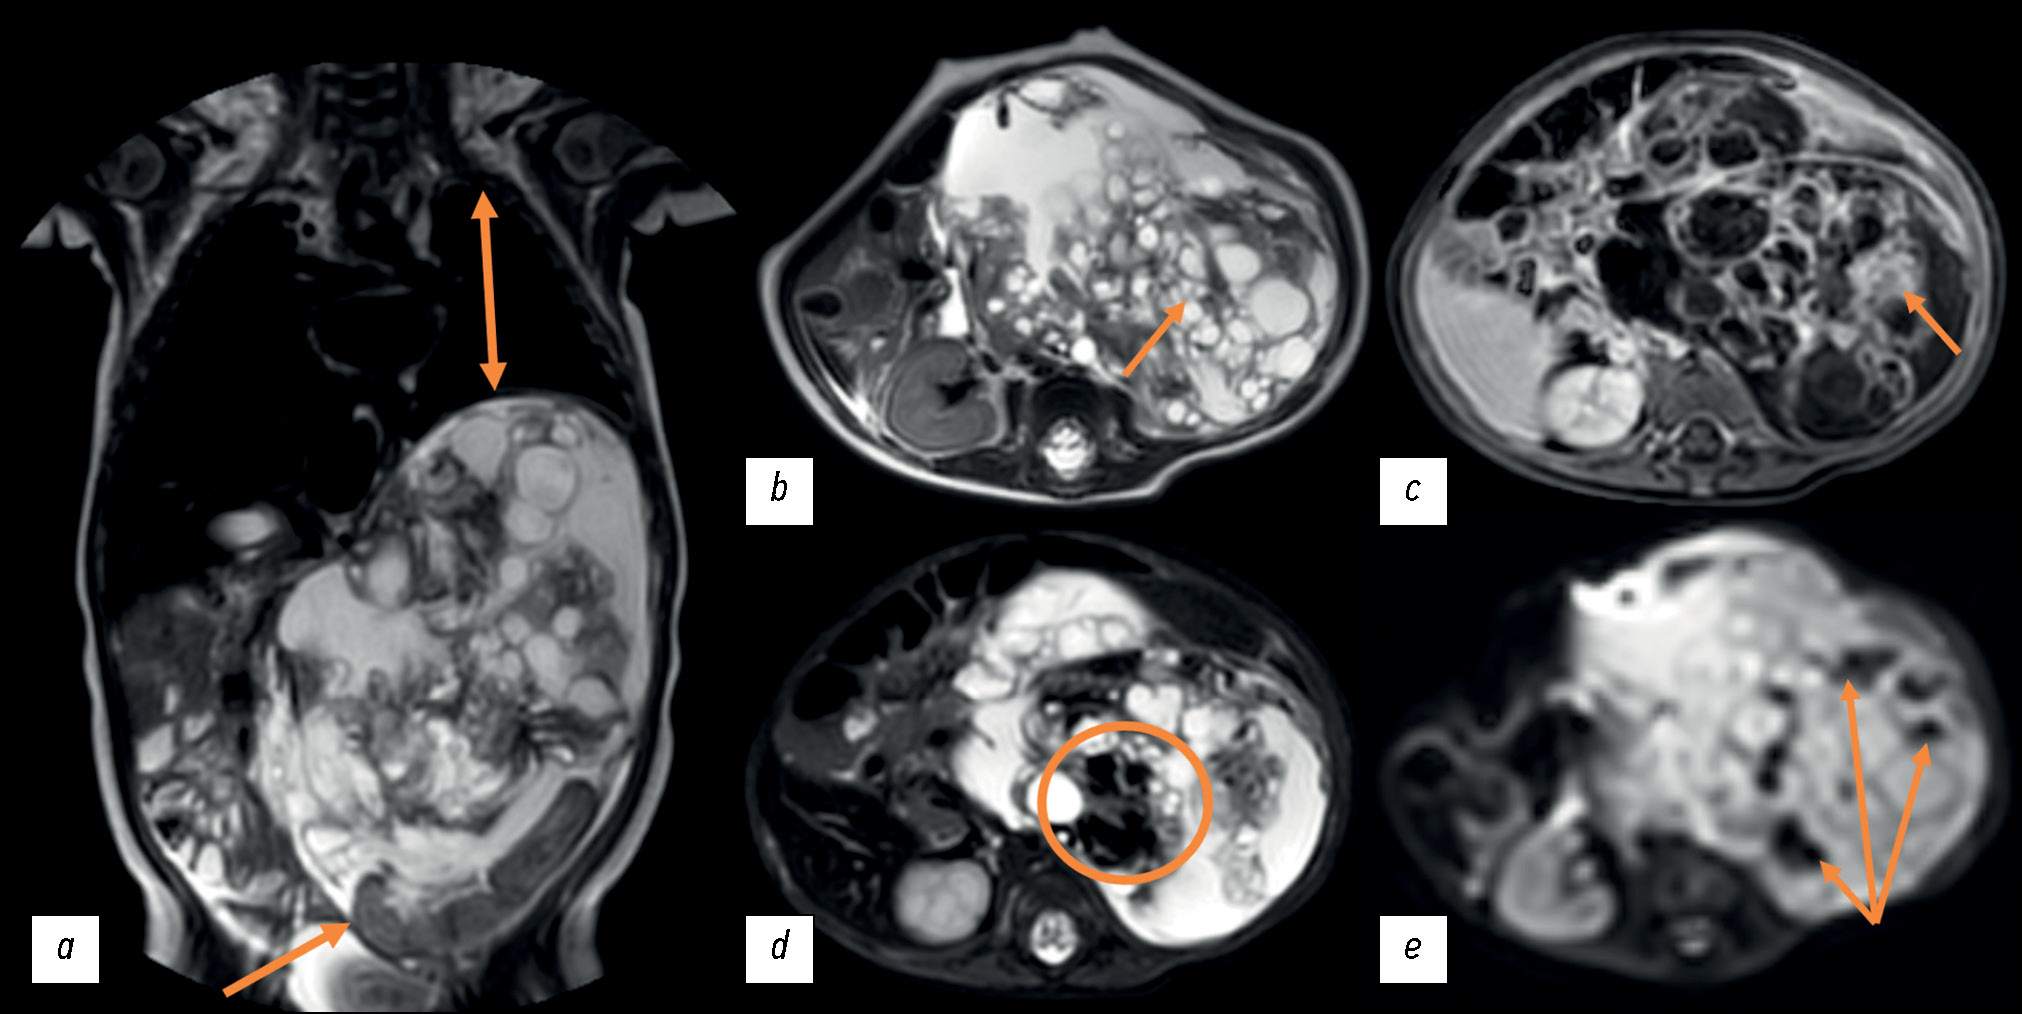

October 16, 2020: The patient was referred for follow-up magnetic resonance imaging (MRI) at their place of residence. The MRI revealed disease progression, with a tumor size increase to 104 × 77 × 118 mm (volume: 491 cm3). The tumor exhibited a cystic and solid structure, with areas of hemorrhage and signs of active contrast uptake. The adrenal gland was spread along the lateral contour of the tumor. The tumor contour was followed by the renal vessels on the left; the superior mesenteric artery was displaced to the right, and the celiac artery was displaced upward. The study did not incorporate contrast sequences or weighted sequences with fat suppression (Fig. 2).

Fig. 2. Abdominal magnetic resonance imaging dated November 16, 2020: (a) Т1-weighted image, sagittal plane; (b) Т2-weighted image, sagittal plane; (c, d) Т1-weighted images, axial plane; a space-occupying mass of the left adrenal gland, with an increase in the size over time. Orange arrows indicate an attenuated signal from the cystic tumor component; the blue arrow indicates an enhanced signal from the solid tumor component.

November 1, 2020: A contrast-enhanced MRI was conducted as a follow-up to ascertain the type of the tumor. A series of abdominal scans revealed persistent signs of a cystic and solid retroperitoneal mass lesion on the left, which was irregularly shaped had relatively clear and smooth contours with areas of intratumor hemorrhage (restricted diffusion areas in diffusion-weighted images) and fat deposits (signal dropout in the spectral pre-saturation with inversion recovery (SPIR) mode). The total dimensions of the lesion were up to 89 × 112 × 141 mm (volume: 731 cm3). The tumor volume increased by 49% in comparison to the previous investigation. A focal MRI contrast absorption in solid components was observed because of intravenous contrast enhancement. The tumor caused caudal displacement of the left kidney to the small pelvic area. The left adrenal gland was not visualized. The spleen was displaced forward, and the tumor margin was clearly visible. The celiac artery followed the medial contour, while the spleen vessels followed the anterior tumor contour. The pancreas extended across the anterior tumor contour and was in close proximity to the tumor. The caudal misplacement of the left hemidiaphragm was a result of the tumor’s upper margin being contiguous to it, which in turn reduced the volume of the left lung (Fig. 4).

Fig. 4. Contrast-enhanced abdominal magnetic resonance imaging dated November 11, 2020, coronal (a) and axial (b–e) planes: (a) Т2-weighted image; diminished volume of the left lung caused by the tumor pressing on the left hemidiaphragm (double orange arrow), displacement of the left kidney to the pelvic area (orange arrow); (b) Т2-weighted image; multiple cysts in the tumor (orange arrow); (c) Т1-weighted image +С; focal contrast uptake in solid components (orange arrow); (d) T2 SPIR; signal dropout because of fat deposits in the tumor (orange circle); (e) diffusion-weighted image; restricted diffusion areas due to intratumor hemorrhages (orange arrows).